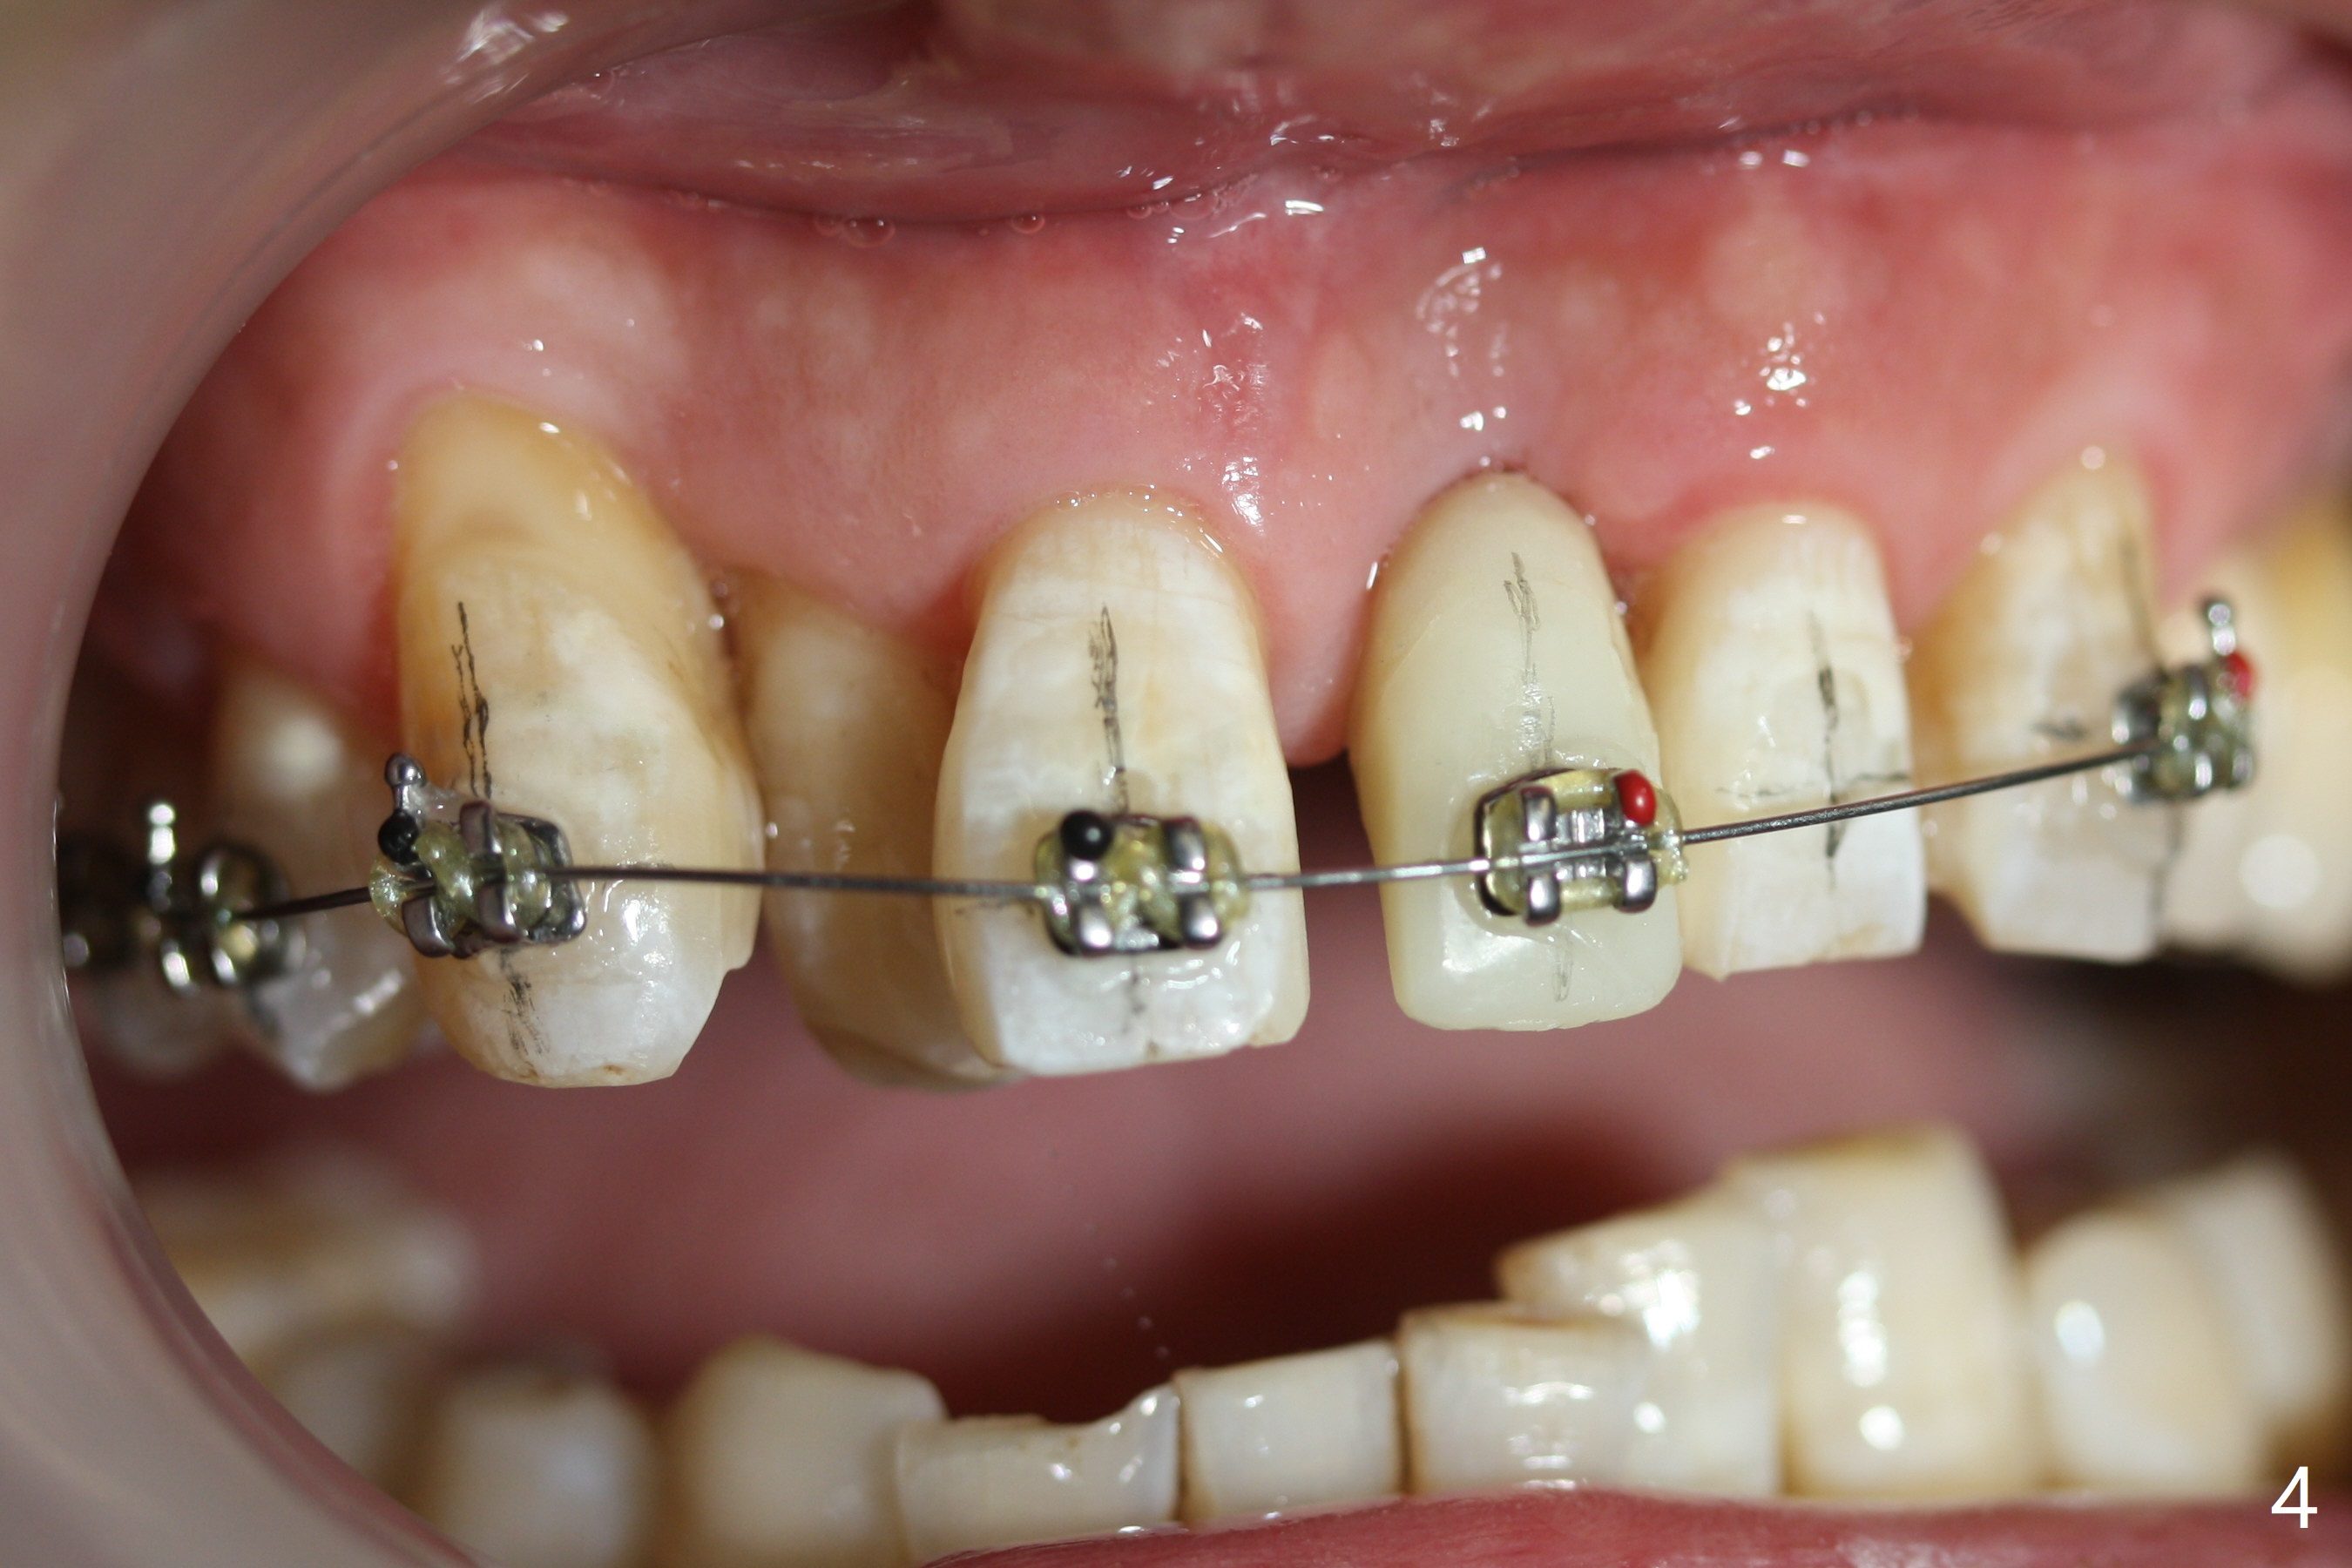

Reduction